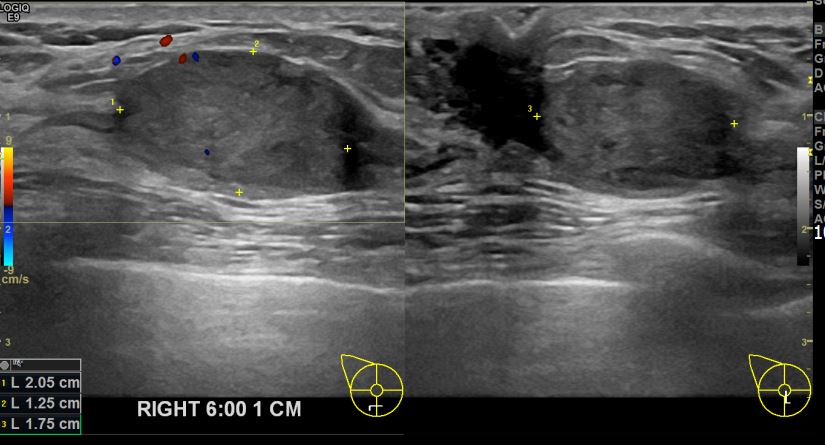

상기환자 우측유방멍울만져져 내원하신 40대 여성분으로 유방암 의심혹 조직검사 시행 후 유방암 진단되었습니다.